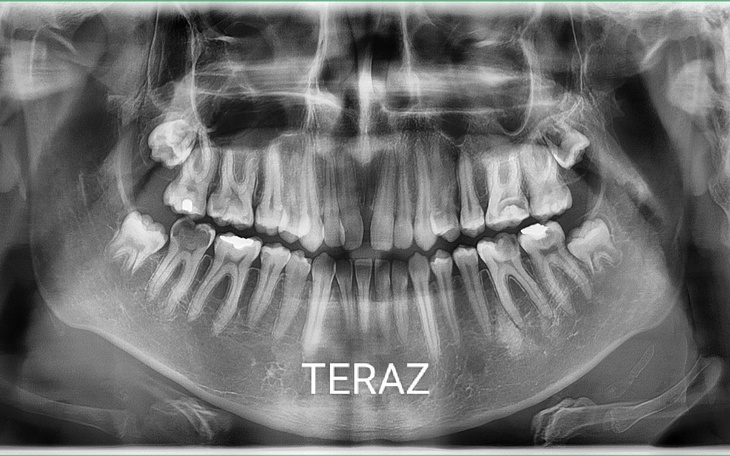

Zbieram na leczenie zębów w znieczuleniu ogólnym. Niestety mam silną dentofobię, przez moje dotychczasowe doświadczenia z stomatologami. Miałem wyrywaną zęba siódemkę i spotkałem się z bardzo złym potraktowaniem i wyrwaniem zęba prawie na żywca. Jestem młodym chłopakiem i chciałbym mieć zdrowy uśmiech, jedyna szansa to leczenie w znieczuleniu ogólnym. Niestety jest to duża kwota w tej chwili dla mnie nie osiągalna do zdobycia. Niestety nie mogę liczyć na pomoc rodziny w tej kwestii. Proszę o chociaż drobną cegiełkę.